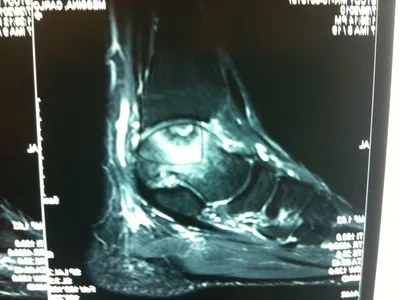

A series of intraop ankle arthroscopy pics of synovial chondromatosis with OCD talus and tibia and microfracture.

Pic of an OCD in the talar dome due to pressure from the nodule.